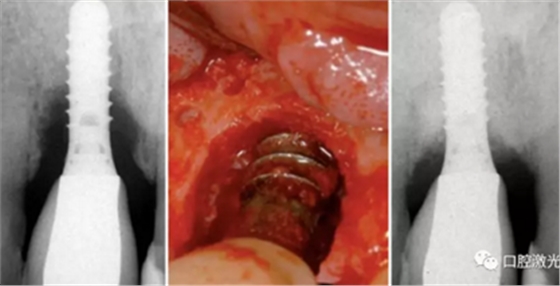

手术阶段的目标是为了能够接触到种植体的全部表面部位。从而可以完全去除结石,并且实施激光灭菌。手术介入治疗是针对那些在初始阶段治疗效果不明显的患者。通过内切翻瓣,暴露整个种植体表面。小心去除种植体周围的肉芽组织,如果在种植体表面看到结石附着,可以通过超声或铒激光进行去除。随后,对种植体表面的剩余物质进行激光照射灭菌。功率2W,连续模式照射10秒钟,快速移动光纤尖,避免种植体表面温度过高。

激光辅助种周炎手术治疗前,中和手术后4年